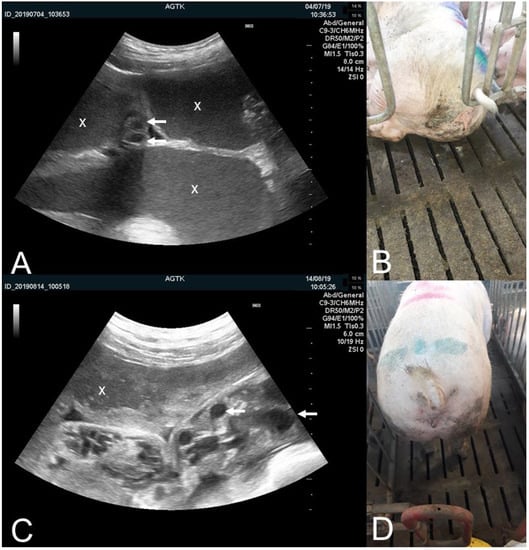

3.1.1. The Pregnant Uterus, Pregnancy Determination and Peripartum Assessment

3.1.2. The Puerperal Uterus